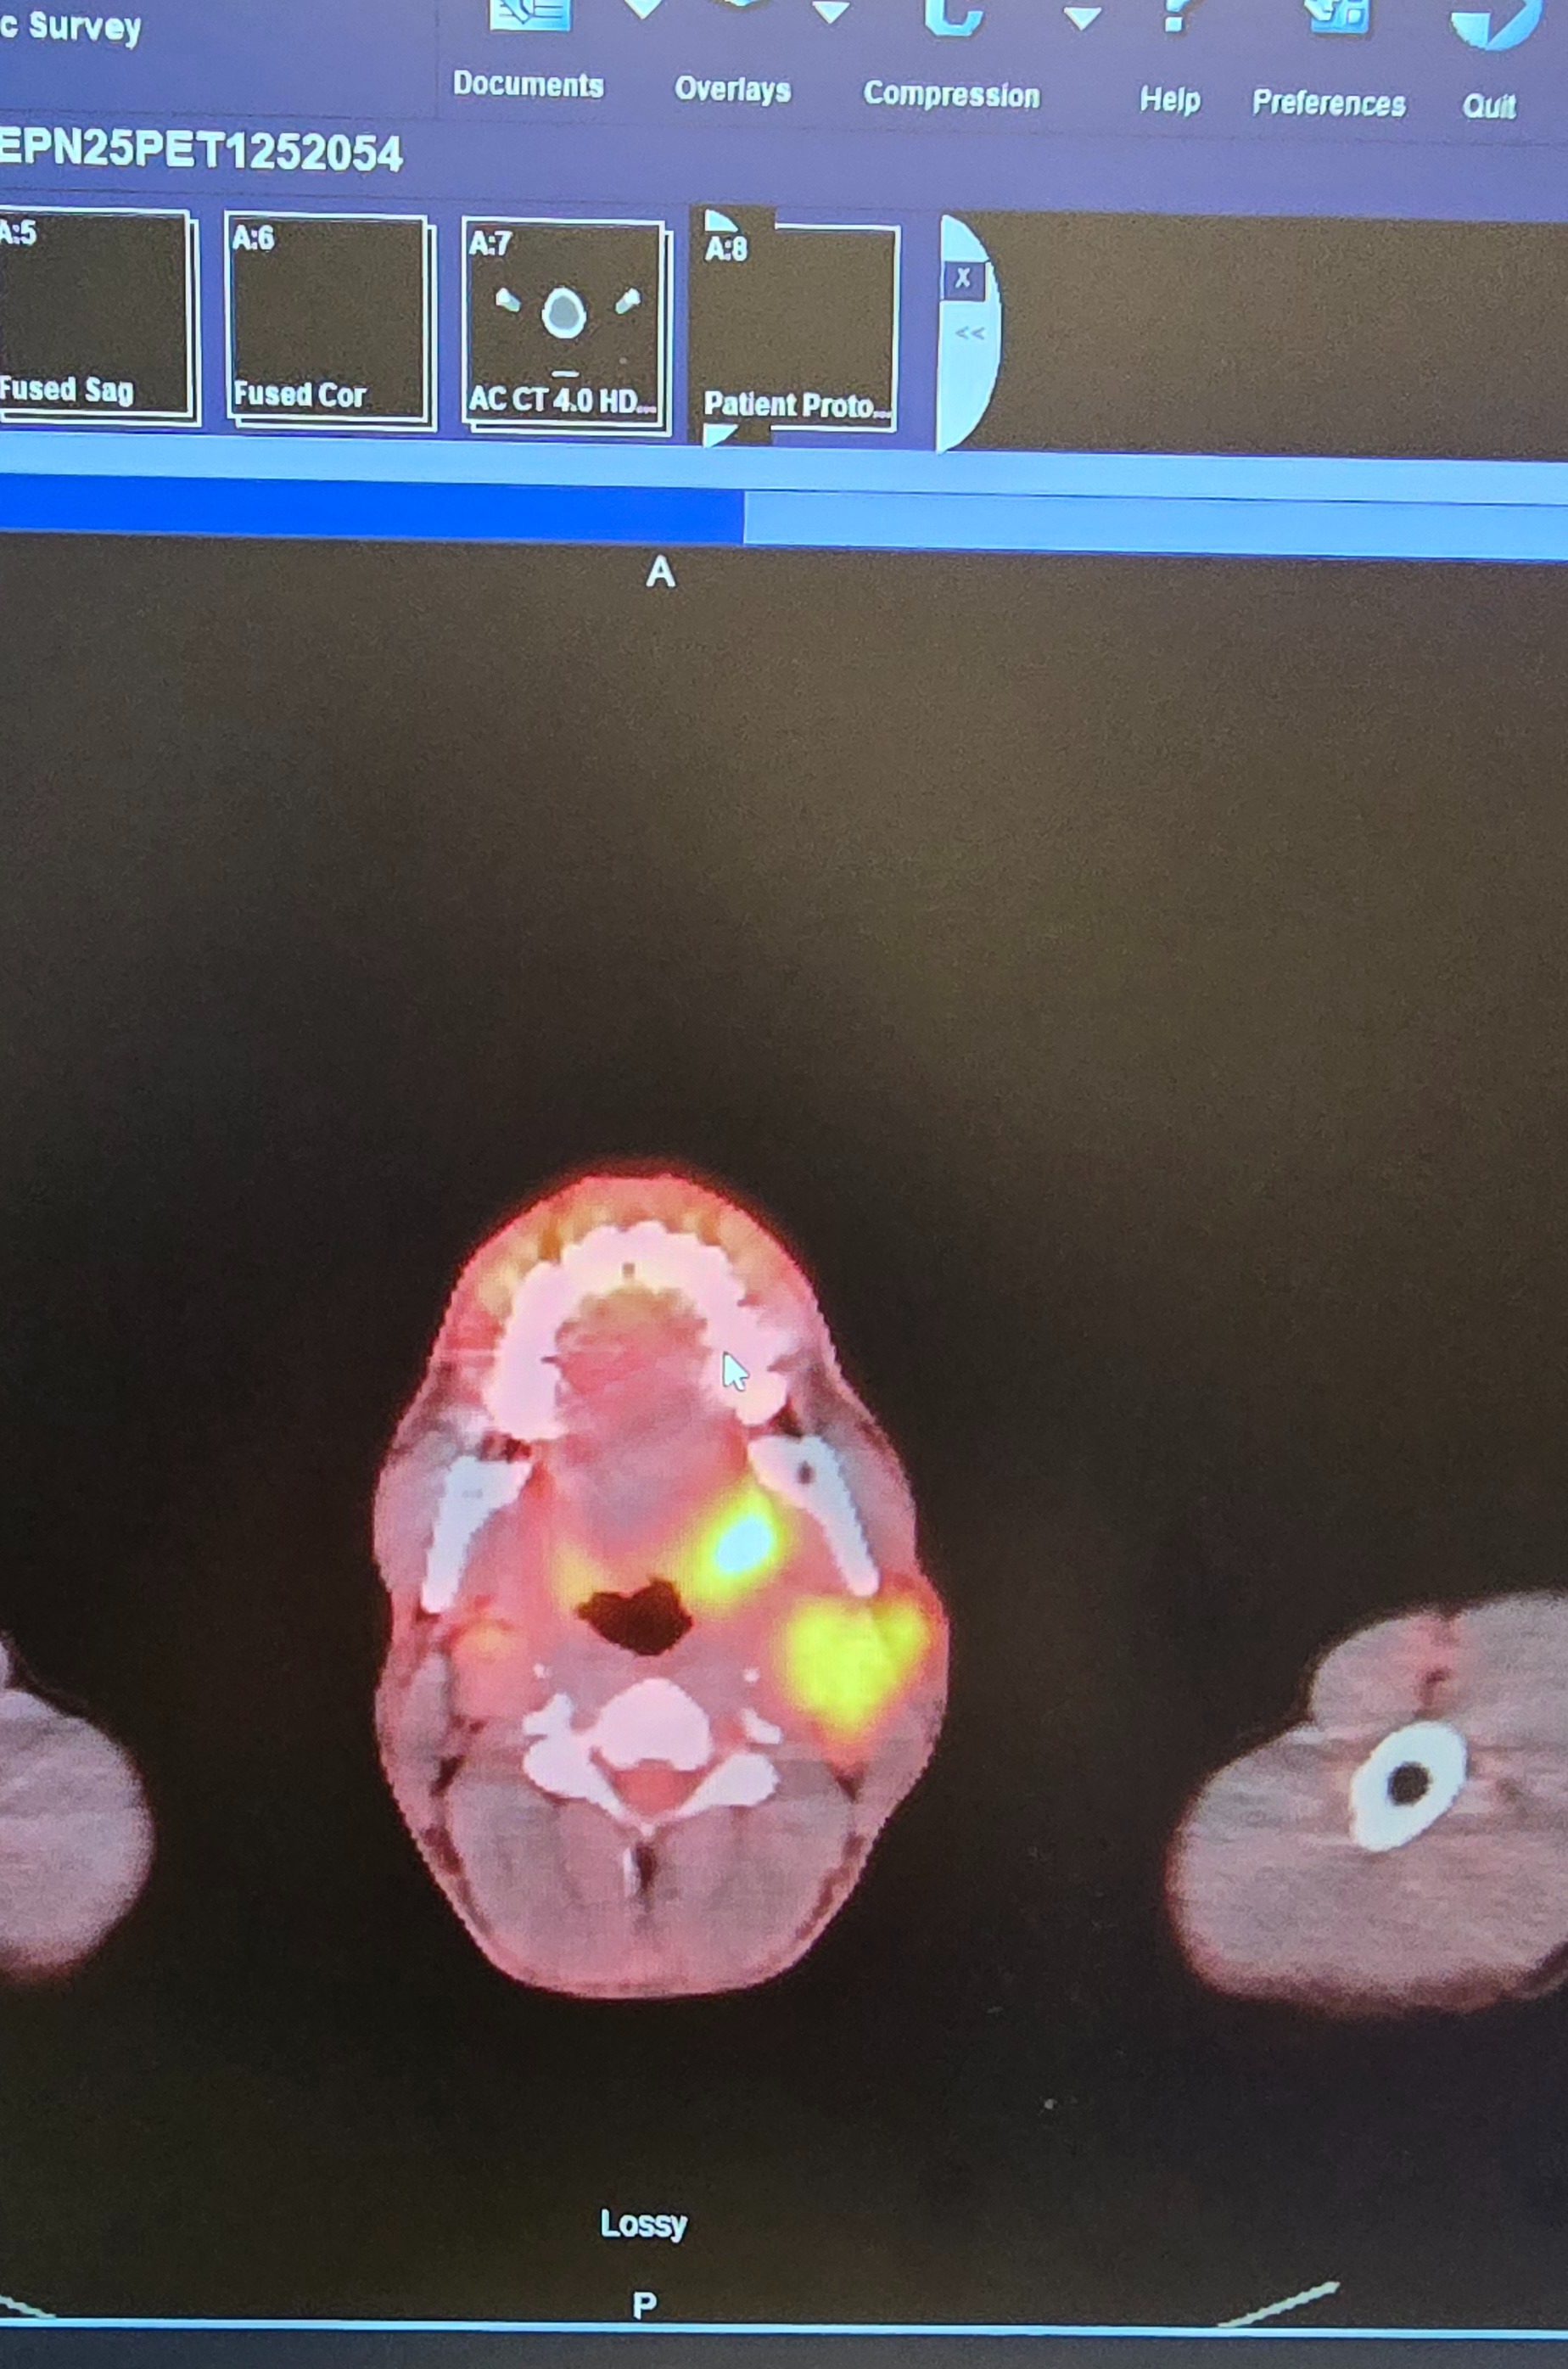

My name is Shane, and on October 30th, I was diagnosed with metastatic poorly differentiated non keratinizing squamous cell carcinoma. Since then, my life has changed dramatically. I am currently undergoing weekly chemotherapy and daily radiation treatments, which has made it impossible for me to work. The physical and emotional toll of treatment is challenging, and the uncertainty about my health and future can feel overwhelming at times.